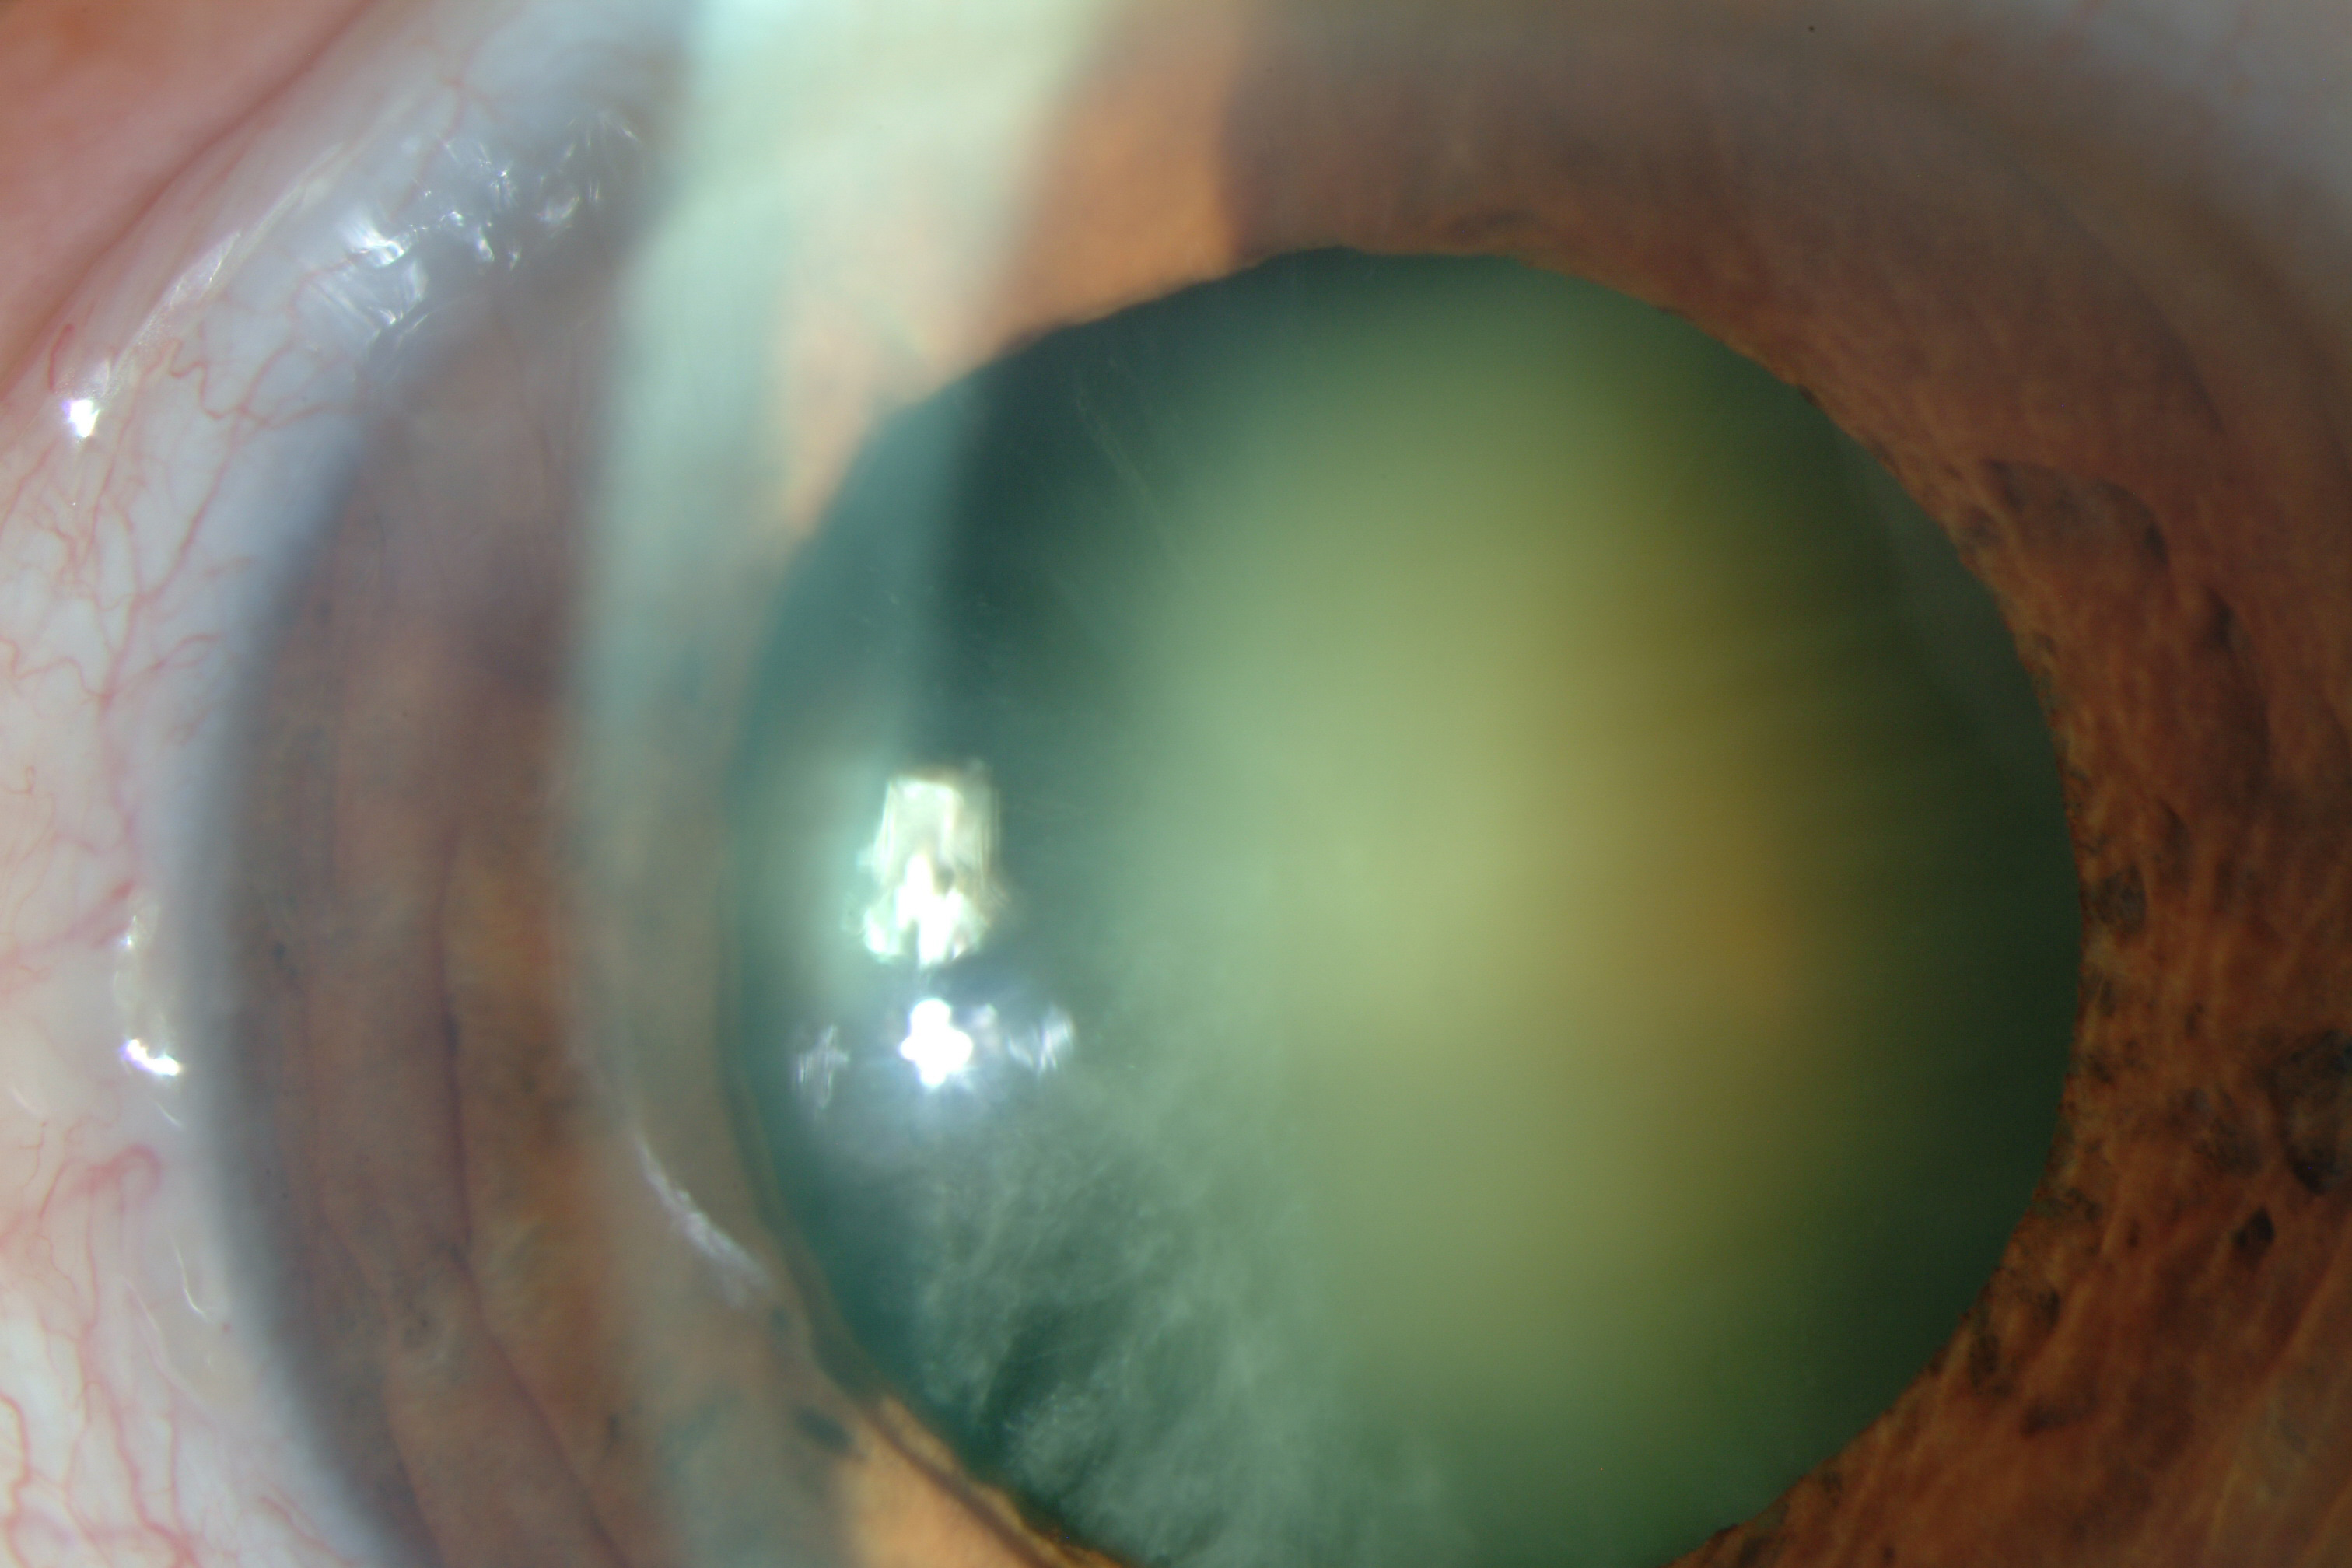

Catarata

La catarata es la opacidad parcial o total del cristalino que se manifiesta por una pérdida de visión progresiva. En la mayoría de casos, la catarata suele aparecer con el envejecimiento a partir de los 60 años. Existen diversos factores que pueden adelantar y acelerar la formación de una catarata como el tabaco, alcohol, exposición solar, tratamiento con corticoides, diabetes y traumatismos oculares. También existen cataratas congénitas.

Catarata